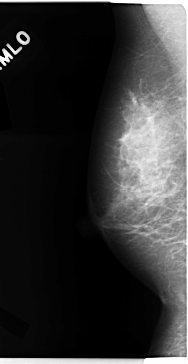

C_0113_1.RIGHT_MLO

RIGHT_CC LINES 4704 PIXELS_PER_LINE 2656 BITS_PER_PIXEL 12 RESOLUTION 50 NON_OVERLAY

RIGHT_MLO LINES 4728 PIXELS_PER_LINE 2432 BITS_PER_PIXEL 12 RESOLUTION 50 NON_OVERLAY